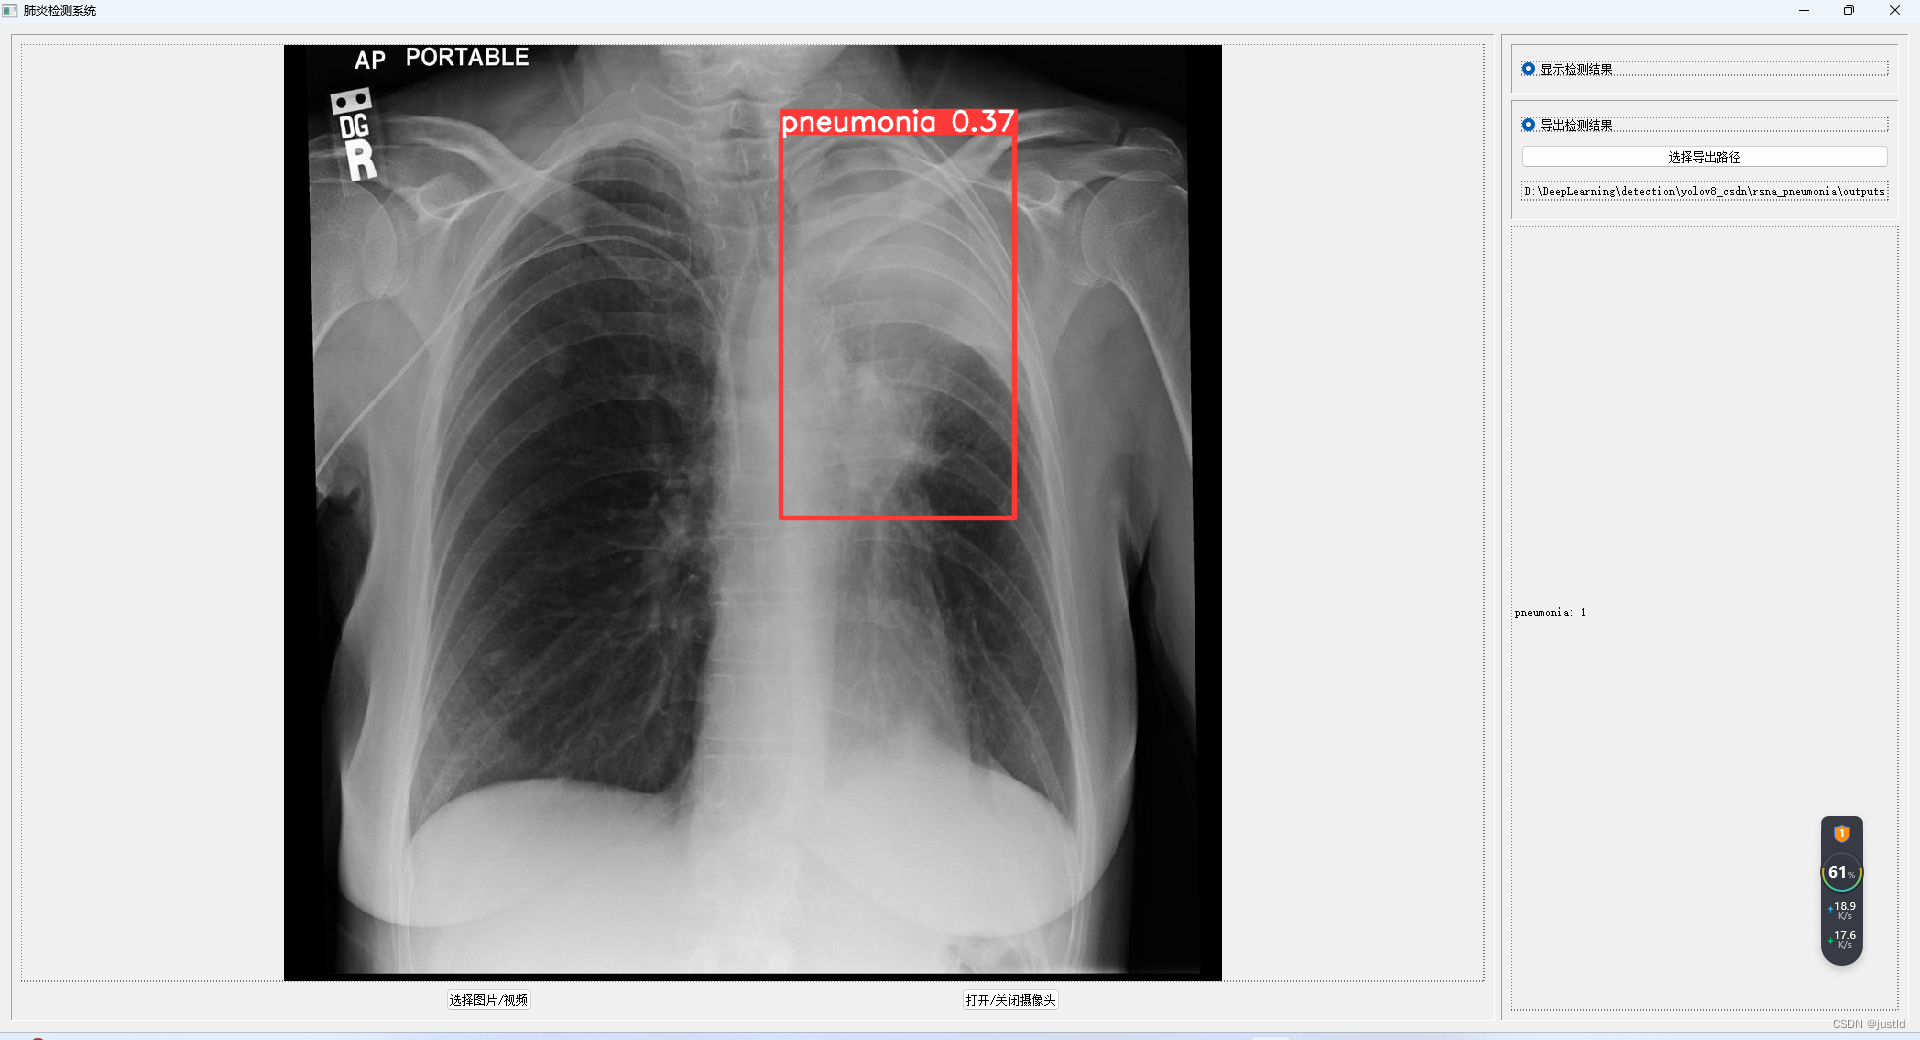

检测结果如下图:

使用pyqt5开发gui界面,支持图片、视频、摄像头输入,支持导出到指定路径,其GUI如下图(完整GUI代码可在下方链接下载):